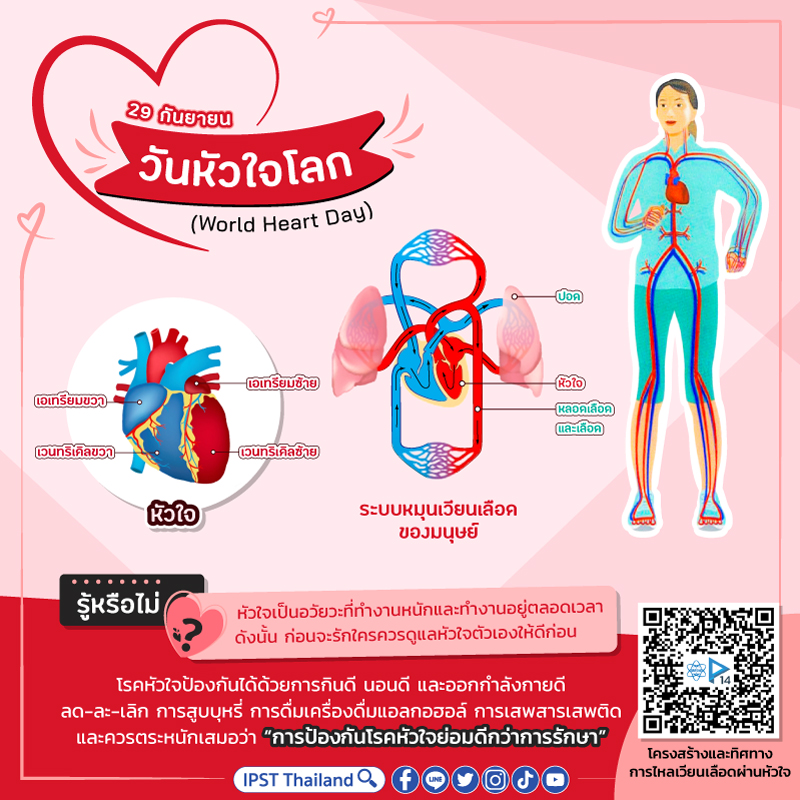

37,900+ การไหลเวียนของเลือด ภาพถ่ายสต็อก รูปภาพ และภาพปลอดค่าลิขสิทธิ์ … หัวใจกับการไหลเวียนของเลือด – ระบบไหลเวียนโลหิต

หัวใจกับการไหลเวียนของเลือด – ระบบไหลเวียนโลหิต ม.2 ระบบหมุนเวียนเลือด | Science – Quizizz

ม.2 ระบบหมุนเวียนเลือด | Science – Quizizz ระบบไหลเวียนเลือด: หัวใจ

วันหัวใจโลก | Oldeenglishconsortium รูปแบบการสอนแบบระบบไหลเวียนโลหิตของมนุษย์ / การสอนแบบจำลองการไหลเวียนโลหิต

แบบจำลองระบบหมุนเวียนโลหิตของมนุษย์ – EnterCenterShop ระบบหมุนเวียนโลหิต

ระบบหมุนเวียนโลหิต 📝โน๊ตสรุประบบหมุนเวียนเลือด… – สภาติวเตอร์ By TS Council | Facebook